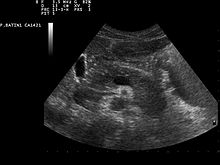

Zur Erkennung von Tumoren der Bauchspeicheldrüse werden bildgebende Verfahren wie Sonografie, Computertomographie, Magnetresonanztomographie sowie ein kombiniertes endoskopisch-radiologisches Verfahren, die sogenannte Endoskopisch retrograde Cholangiopankreatikographie, genutzt.[50] Darüber hinaus kann mittels Bauchhöhleneröffnung (Laparotomie) und -spiegelung (Laparoskopie) das Organ direkt beurteilt werden. Die Flexible Transgastrische Peritoneoskopie ist ein im Experimentalstadium befindliches Untersuchungsverfahren. Auch Pankreaspseudozysten, Pankreassteine (deren sicherer Nachweis erst nach Einführung der Röntgendiagnostik, etwa durch Arthur Mayo-Robson,[53] möglich wurde) oder Pankreasverkalkungen können mit den genannten bildgebenden Verfahren erkannt werden. Als brauchbarer Tumormarkerhat sich CA 19-9 bewährt.[54]